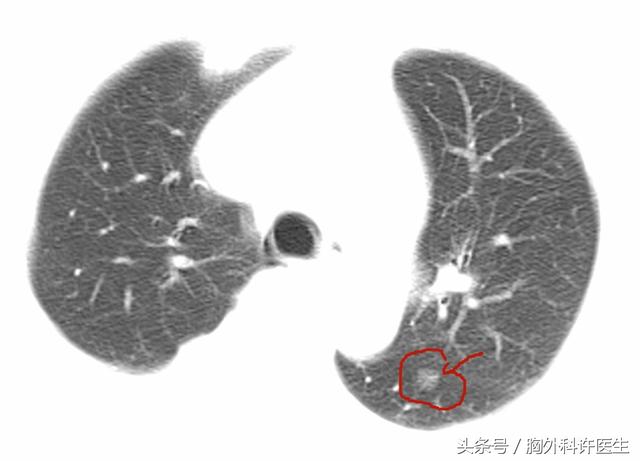

左下肺磨玻璃结节